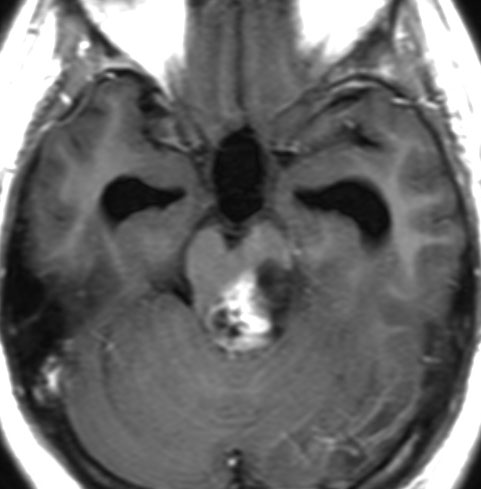

頭部打撲で検査され偶然発見された19歳男性ものです。中脳視蓋全体が腫大して腫瘍化しています。左側にのう胞があり周囲が淡くガドリニウムで増強されます。

中脳水道の癒着閉塞により,高度の停止性水頭症になっています。高身長ですが頭囲が61cmありました。小さい頃から頭が大きいので家族も気にならないようです。数年以上あるいは10年近くの長期にわたってこの水頭症は変わらないのでしょう。

頭痛などの症状はなく,眼底所見も視神経乳頭の異常はありませんでした。無治療で経過観察をしています。認知機能も全く正常で,国立大学から大学院に進む予定です。